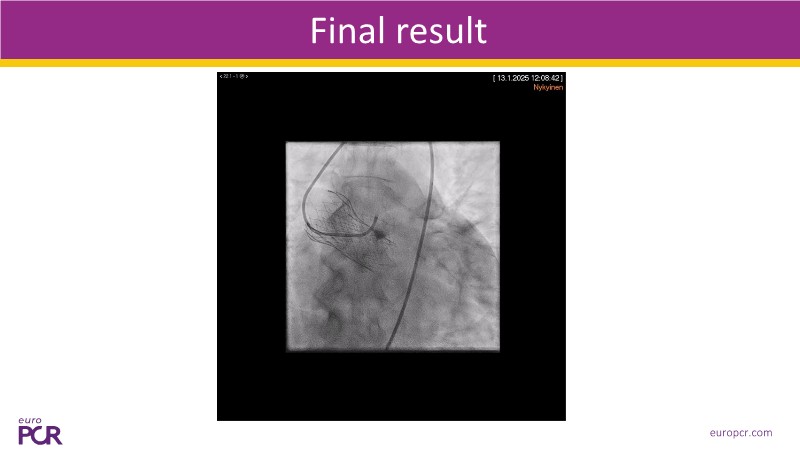

This session explores some of the most clinically complex scenarios encountered in TAVI practice. Three real-world cases address key challenges such as intervention sequencing and transcatheter valve selection in patients with combined coronary artery disease and severe aortic stenosis. The session also examines coronary obstruction risk assessment and protection strategies during redo TAVI, and discusses specific implantation techniques for anatomically complex cases, including large aortic valve anatomy.